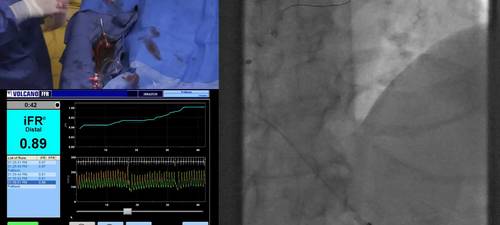

A demonstration of how to check and document pressure wire drift after assessing an artery